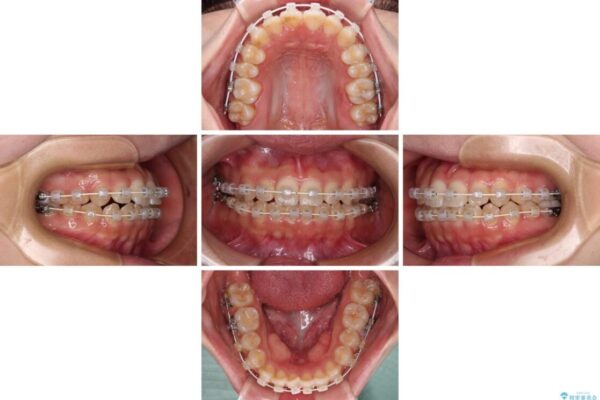

治療途中

• 【モニター】短期間で終わりたい ワイヤー装置での非抜歯矯正 治療途中画像